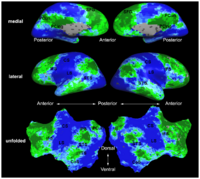

Brain ConnectivityPlaceholder for Archana's project New: A. Venkataraman, Y. Rathi, M. Kubicki, C-F. Westin and P. Golland. Joint Generative Model for fMRI/DWI and its Application to Population Studies. In Proc. MICCAI: International Conference on Medical Image Computing and Computer Assisted Intervenion, LNCS 6361:191-199, 2010. New: A. Venkataraman, M. Kubicki, C.-F. Westin, and P. Golland. Robust Feature Selection in Resting-State fMRI Connectivity Based on Population Studies. In Proc. MMBIA: IEEE Computer Society Workshop on Mathematical Methods in Biomedical Image Analysis, 2010. A. Venkataraman, K.R.A Van Dijk, R.L. Buckner, and P. Golland. Exploring functional connectivity in fMRI via clustering. In Proc. ICASSP: IEEE International Conference on Acoustics, Speech and Signal Processing, 441-444, 2009. Y. Golland, P. Golland, S. Bentin, and R. Malach. Data-driven clustering reveals a fundamental subdivision of the human cortex into two global systems. Neuropsychologia, 46(2):540-553, 2008. P. Golland, Y. Golland, R. Malach. Detection of Spatial Activation Patterns As Unsupervised Segmentation of fMRI Data. In Proc. MICCAI: International Conference on Medical Image Computing and Computer Assisted Intervention, LNCS 4791:110-118, 2007. | |

Improving fMRI Analysis using Supervised and Unsupervised LearningOne of the major goals in the analysis of fMRI data is the detection of networks in the brain with similar functional behavior. A wide variety of methods including hypothesis-driven statistical tests, supervised, and unsupervised learning methods have been employed to find these networks. In this project, we develop novel learning algorithms that enable more efficient inferences from fMRI measurements. More... New: G. Langs, Y. Tie, L. Rigolo, A.J. Golby, and P. Golland. Functional Geometry Alignment for Localization of Brain Areas. To appear in Proc. NIPS: Neural Information Processing Systems, 2010. New: A. Venkataraman, Y. Rathi, M. Kubicki, C-F. Westin and P. Golland. Joint Generative Model for fMRI/DWI and its Application to Population Studies. In Proc. MICCAI: International Conference on Medical Image Computing and Computer Assisted Intervention, LNCS 6361:191-199, 2010. New: D. Lashkari, E. Vul, N.G. Kanwisher, and P. Golland. Discovering structure in the space of fMRI selectivity profiles. NeuroImage, 3(15):1085-1098, 2010. New: A. Venkataraman, M. Kubicki, C.-F. Westin, and P. Golland. Robust Feature Selection in Resting-State fMRI Connectivity Based on Population Studies. In Proc. MMBIA: IEEE Computer Society Workshop on Mathematical Methods in Biomedical Image Analysis, 2010. New: D. Lashkari, R. Sridharan, E. Vul, P.-J. Hsieh, N. Kanwisher, and P. Golland. Nonparametric Hierarchical Bayesian Model for Functional Brain Parcellation. In Proc. MMBIA: IEEE Computer Society Workshop on Mathematical Methods in Biomedical Image Analysis, 2010. |

fMRI Detection and AnalysisWe are exploring algorithms for improved fMRI detection and interpretation by incorporting spatial priors and anatomical information to guide the detection. More... New: W. Ou, W.M. Wells III, and P. Golland. Combining Spatial Priors and Anatomical Information for fMRI Detection. Medical Image Analysis, 14(3):318-331, 2010.